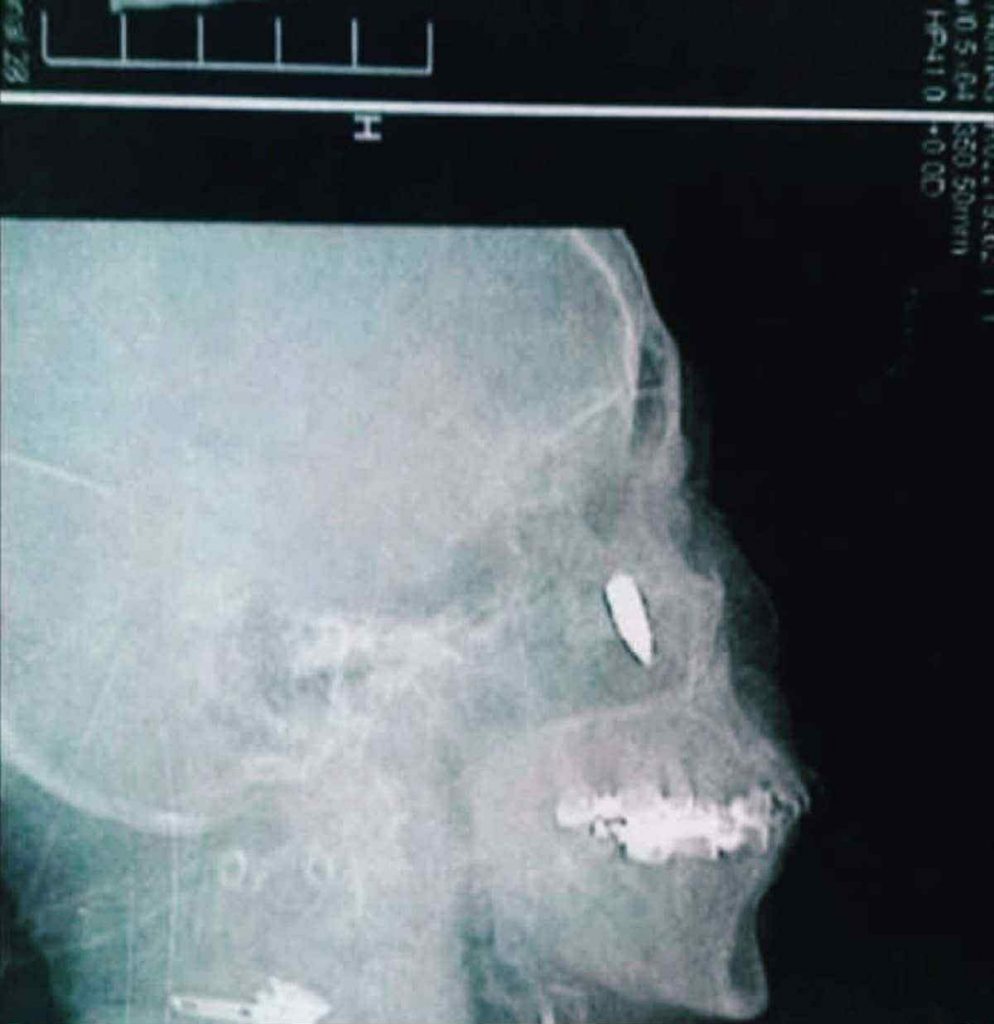

Cítila, jak jí na krk fouká studený vítr, i když v místnosti nebyl žádný vzduch. Lékařka k ní otočila obrazovku – na obraze, mezi měkkými šedými stíny tkáně, se leskl malý, hustý, cizí ovál. Ani kost, ani kámen. Kulka.

Kulka.

Ale teď, o 48 let později, seděla před rentgenem a poprvé se jí zhmotnila vlastní minulost. Kovová.

A toho večera, když seděla u okna, se znovu podívala na fotografii. Malý úlomek kovu. Téměř tečka. Ale kolik ticha jí do života vnesla? Kolik bolesti vysvětlila? Kolik otázek vyvolala, které si předtím neodvážila položit?